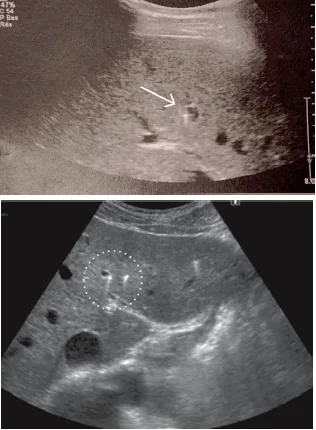

En 2003, l’équipe de Saint-Antoine a comparé 18 patients porteurs de la mutation ABCB4 à des patients atteints de lithiase biliaire banale [1]. Cette équipe a ainsi pu rapporter pour la première fois que la présence d’au moins 2 des 3 critères suivants était fortement associée à la mutation ABCB4 : 1) début des symptômes avant l’âge de 40 ans ; 2) récidive des symptômes après cholécystectomie ; 3) mise en évidence par échographie de foyers hyper-échogènes intra-hépatiques avec, soit des renforcements postérieurs (« queues de comète ») correspondant à des dépôts canalaires de cristaux de cholestérol, soit des cônes d’ombre correspondant à des calculs ou micro-calculs (Fig. 2 et 3). Par ailleurs, la même équipe a montré que les caractéristiques cliniques, radiologiques et de l’analyse de la bile des patients atteints de syndrome LPAC sans mutation ABCB4 étaient identiques à celles des patients mutés pour ABCB4 [4].

3) C’est la réalisation d’une échographie par un opérateur sensibilisé à la recherche des signes évocateurs qui est, en pratique, le moyen le plus pertinent pour confirmer le diagnostic. En effet, chez les patients atteints de syndrome LPAC avec mutation ABCB4, cette échographie experte révèle des anomalies typiques dans 88 à 95 % des cas (4, étude LPANGH). Cette haute pertinence diagnostique est également retrouvée en cas de syndrome LPAC sans mutation ABCB4 [4]. Le diagnostic radiologique repose sur la mise en évidence de spots hyper-échogènes intra-hépatiques responsables d’images en queue de comète de topographie compatible avec des dépôts de microcristaux le long de l’arbre biliaire (Fig. 2). Il peut aussi s’agir de sludge, d’une micro-lithiase intra-hépatique ou de macro-calculs avec cône d’ombre (Fig. 3). À l’inverse, une échographie pratiquée par un radiologue non expert et non averti du diagnostic supposé de syndrome LPAC (il s’agit le plus souvent d’échographies pratiquées en urgence devant des symptômes biliaires) ne décrira les signes de la maladie que dans 5 % des cas de syndrome LPAC (étude LPANGH).